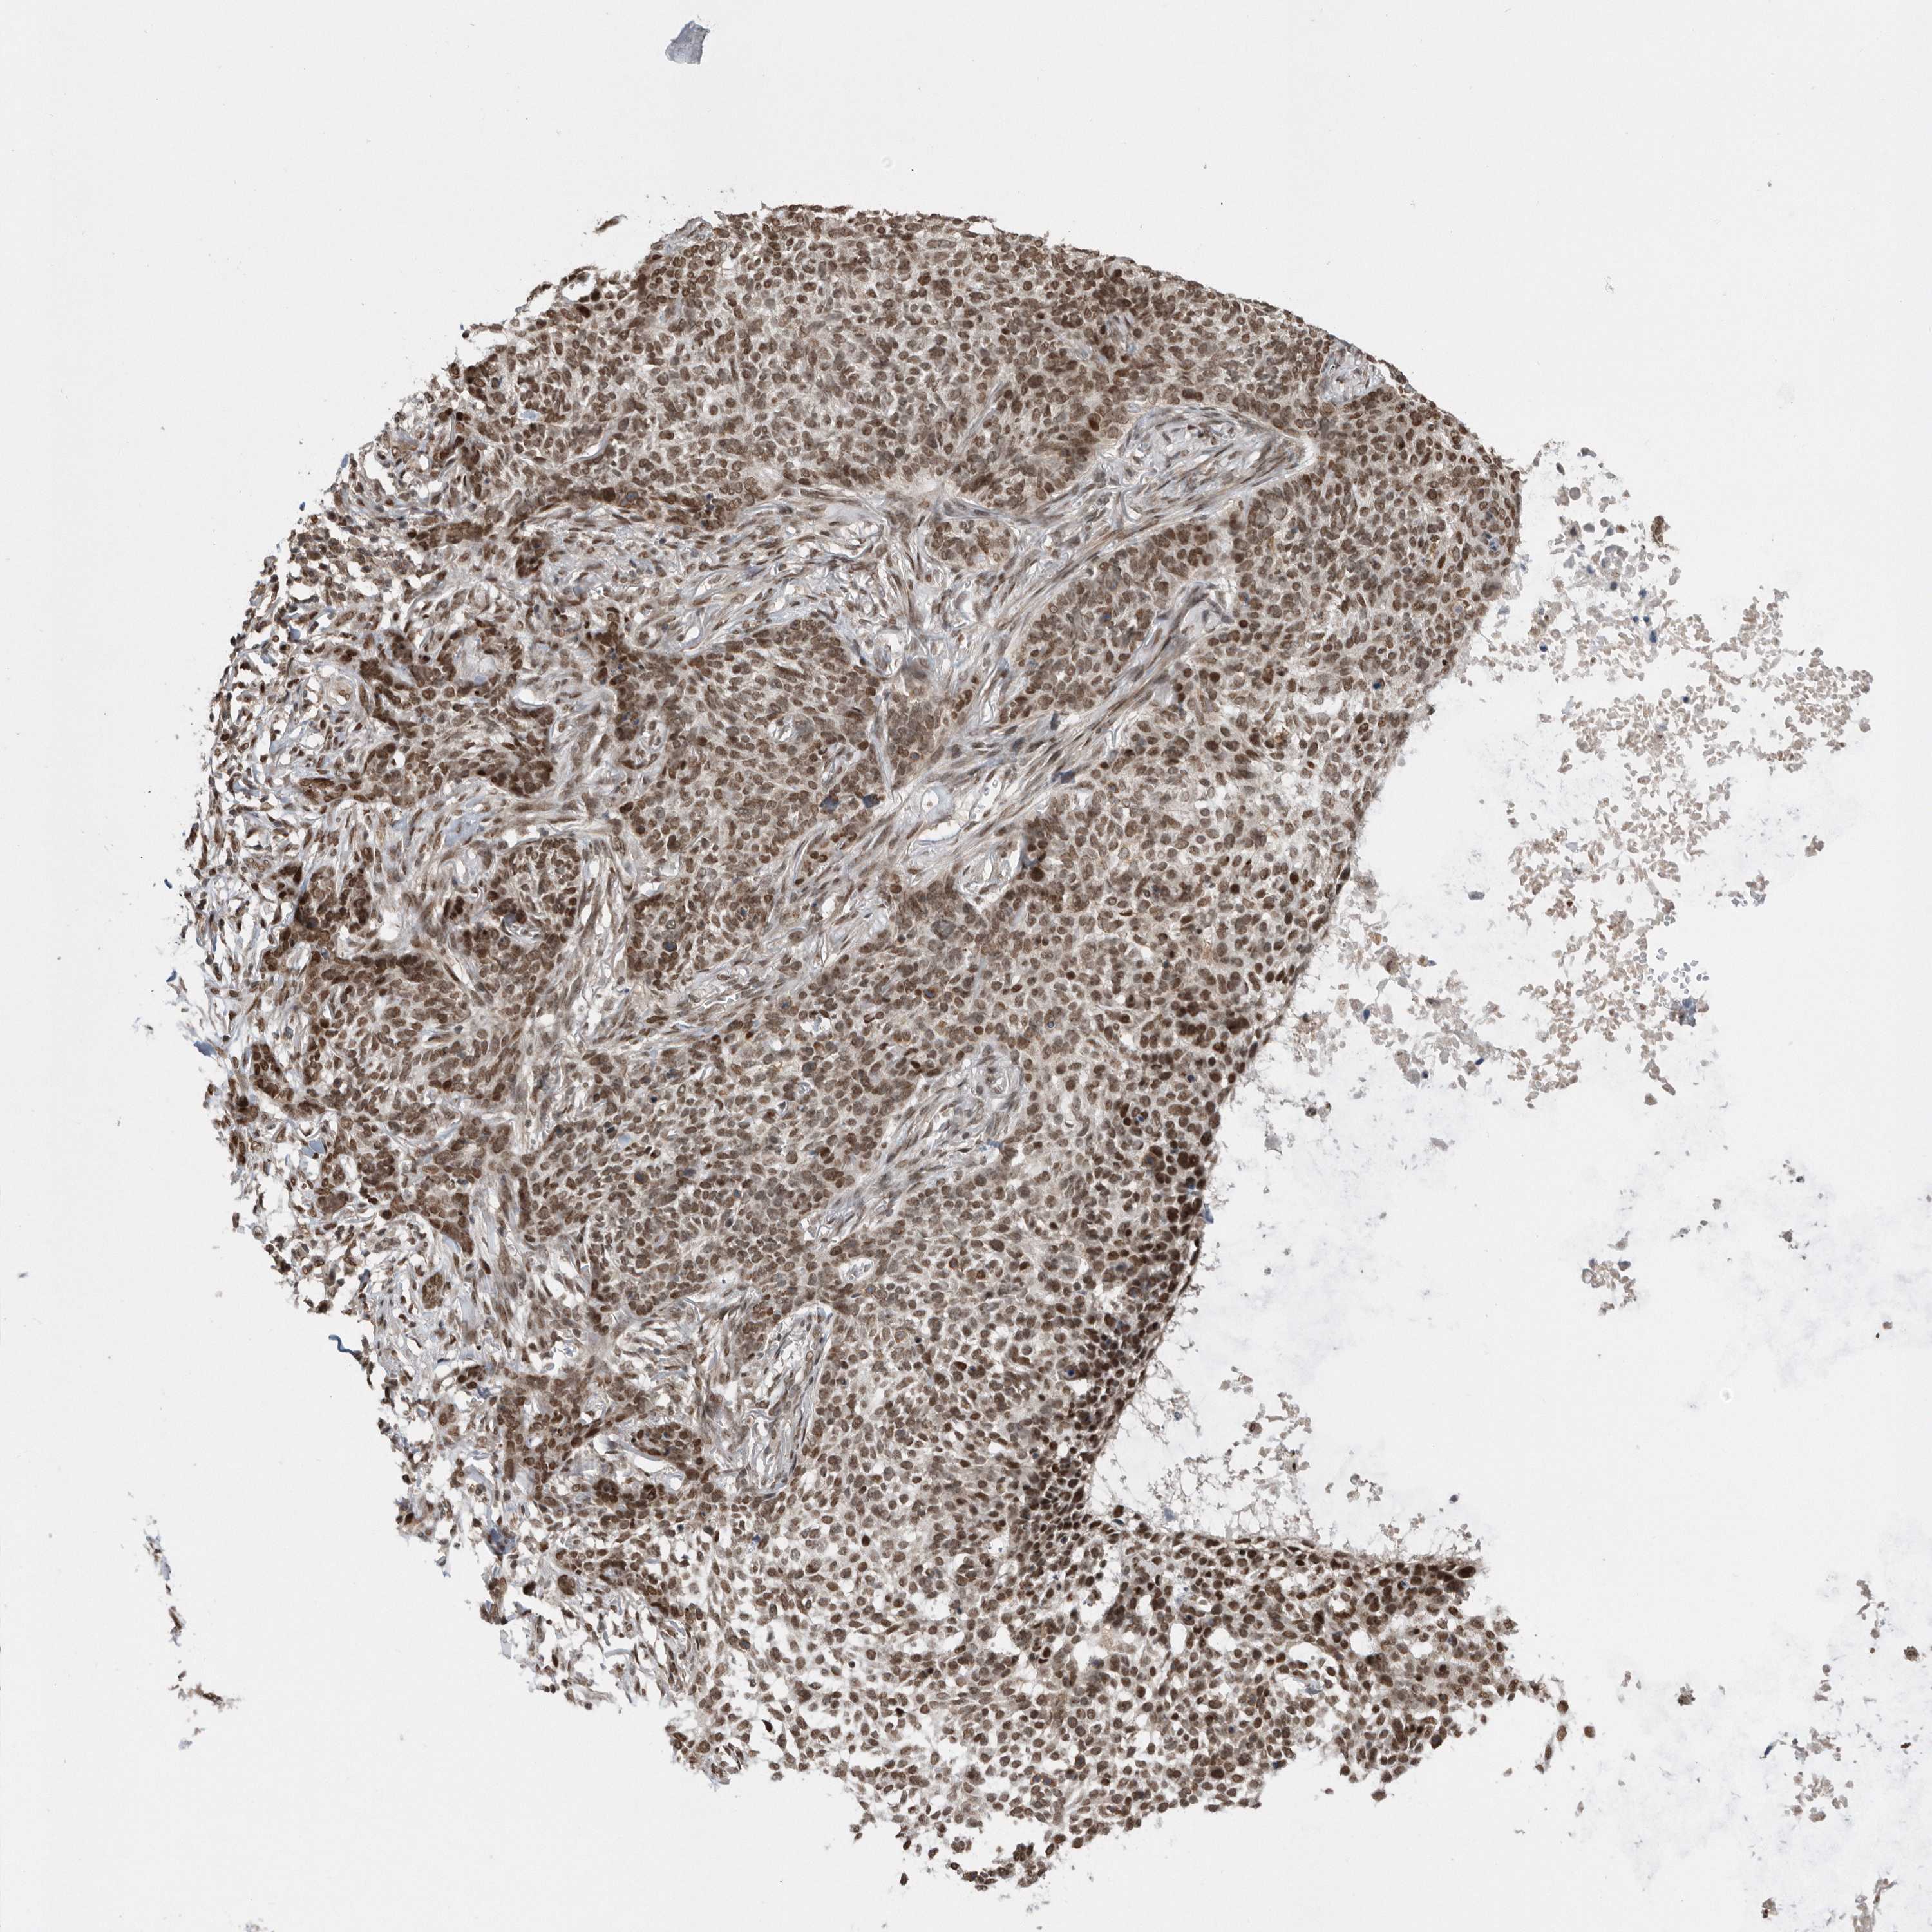

Basal cell and squamous cell cancer

SKIN CANCER - Protein expressioni

A mouse-over function shows sample information and annotation data. Click on an image to view it in a full screen mode. Samples can be filtered based on level of antibody staining by selecting one or several of the following categories: high, medium, low and not detected. The assay and annotation is described here.

Antibody stainingi

Antibody staining in the annotated cell types in the current human tissue is reported as not detected, low, medium, or high, based on conventional immunohistochemistry profiling in selected tissues. This score is based on the combination of the staining intensity and fraction of stained cells.

Each image is clickable and will lead to virtual microscopy that enables deeper exploration of all samples and also displays staining intensity scores, fraction scores and subcellular localization as well as patient and tissue information for each sample.

Antibody CAB034925

Staining

Medium

Intensity

Moderate

Quantity

75%-25%

Location

Nuclear

Squamous cell carcinoma, NOS